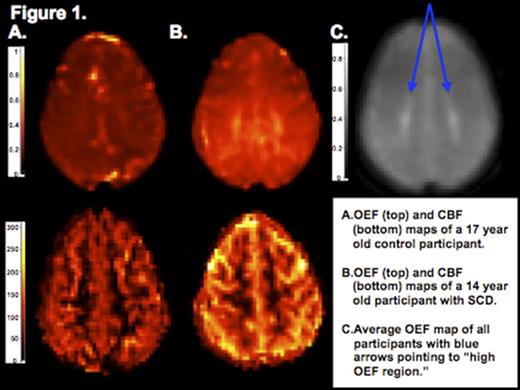

Thirty-six participants, 8 controls and 28 with SCD (26 HbSS and 2 HbSB0), ages 5-21 years, were recruited from St. Louis Children's Hospital. Participants underwent brain MRI with measurement of CBF via pseudo-continuous arterial spin labeling and OEF via a novel processing of asymmetric spin echo sequence that measures tissue deoxyhemoglobin. CBF and OEF maps were individually co-registered to corresponding T1 images with FMRIB's Linear Image Registration Tool, and gray and white matter were segmented with FMRIB's Automated Segmentation Tool. Visual inspection identified a region of high OEF within the deep white matter of the frontal and parietal lobes in the majority of subjects (figure 1 a,b). OEF maps from control and SCD participants were coregistered and averaged into a single map, and then an OEF threshold of 47.5% was applied to demarcate this "high OEF region" (figure 1c). Hemoglobin (Hb) and hematocrit were obtained in SCD participants, while these values were assumed for the controls. Arterial oxygen content (CaO2) was calculated as 1.36 x Hb x SpO2. Comparisons were made with a Mann-Whitney U test or Student's t-test. Bivariate correlations were tested with Kendall's tau b. Bonferroni correction was used in determining significance. Multivariate linear regression modeling with block entry described covariates associated with CBF.

The control and SCD cohorts did not differ in age, gender or SpO2. SCD participants demonstrated higher whole brain, gray matter and white matter CBF and OEF when compared to controls (table 1, figure 1a-b), but there was no difference in whole brain or segmented measures of CBF and OEF between SCD participants with structurally normal brain MRIs (n=16) and silent infarcts (n=12). SCD participants' OEF was higher within the "high OEF region" when compared to controls (table 1), but the regional OEF did not differ between SCD participants with structurally normal brain MRIs versus silent infarcts. Whole brain CBF negatively correlated with age (b = -0.554, p < 0.001), while whole brain OEF did not (b= 0.014, p = 0.921). Lower CaO2 correlated with higher whole brain CBF (b = -0.329, p < 0.016) and higher whole brain OEF (b = -0.587, p < 0.001). CaO2 remained a predictor (β = -0.38, p = 0.009) of CBF when controlling for age (β = -0.63, p < 0.001).